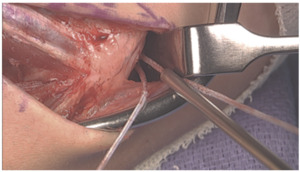

Graft Passage

With the arm held in full supination and 30° of flexion primary repair of the distal footprint tear, if present, is performed.

One arm of the tendon graft is docked, with a #2 ortho cord suture with a baseball stitch with one arm of the internal brace. The second arm of the tendon graft is cut to an appropriate length, and the second #2 Ortho cord suture is placed. The second arm of the tendon graft is then docked proximally, followed by the second arm of the internal brace.

The internal brace suture arms are first tensioned and tied using a knot tier. Five throws are placed in the suture arms. The tendon graft sutures are then tensioned and tied as well. *Note that the internal brace is tensioned and tied first to preset the tension on the joint. (Figure 17)